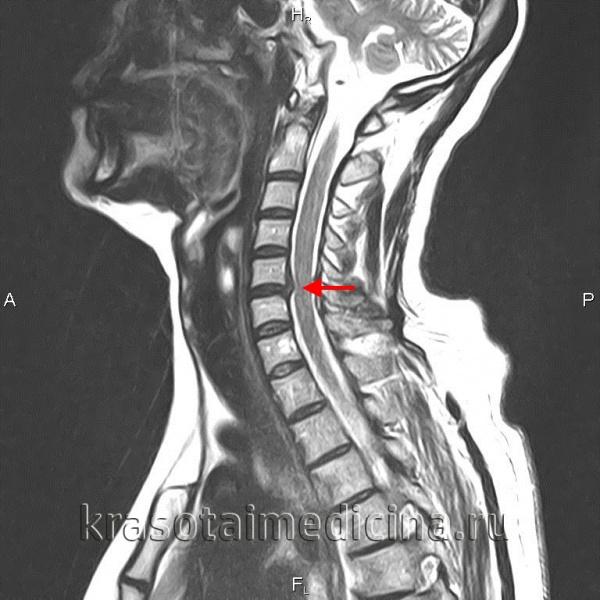

- Диагностика: МРТ, КТ, рентгенография для определения степени повреждения.

Как правильно поставить диагноз?

Врач может назначить одно из следующих инструментальных исследований:

Магнитно-резонансная томография (МРТ) — это безболезненное и неинвазивное исследование, с помощью которого благодаря магнитному полю получают детализированные изображения всех структур тела, включая мягкие ткани. МРТ позволяет визуализировать нервы и межпозвоночные диски, что невозможно с помощью рентгена.

Данное исследование позволяет врачу хорошо рассмотреть все структуры срез за срезом (снимки проводят в виде «срезов» через 1-2 см, как будто рассматривают нарезанный хлеб кусок за куском). Снимки можно делать сверху вниз, сбоку, наискосок. Можно применить внутривенный контраст, или обойтись без него. МРТ показывает, какой именно диск поврежден и есть ли защемление нерва. Кроме того, врач может увидеть костные разрастания, опухоли спинного мозга, абсцессы.

- Магнитно-резонансная томография;

Наиболее полное представление о состоянии хрящевой ткани позвоночника дает МРТ, позволяя получить послойные изображения и точно оценить расположение и размеры выпячивания.